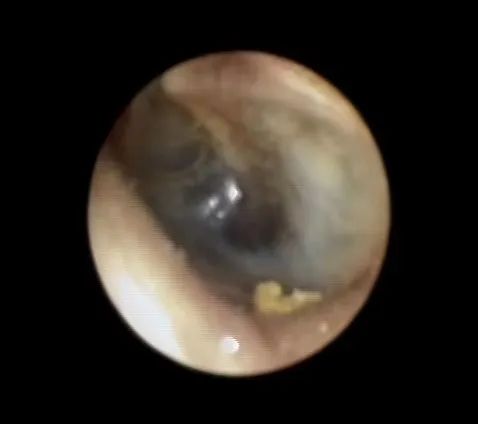

在耳内镜,听力学以及颞骨CT等相关检查后发现,安女士的鼓膜已经明显内陷,鼓室里的积液呈蓝棕色,听力检查提示传导性耳聋,颞骨CT也提示鼓室及乳突里积液。

颞骨CT检查。